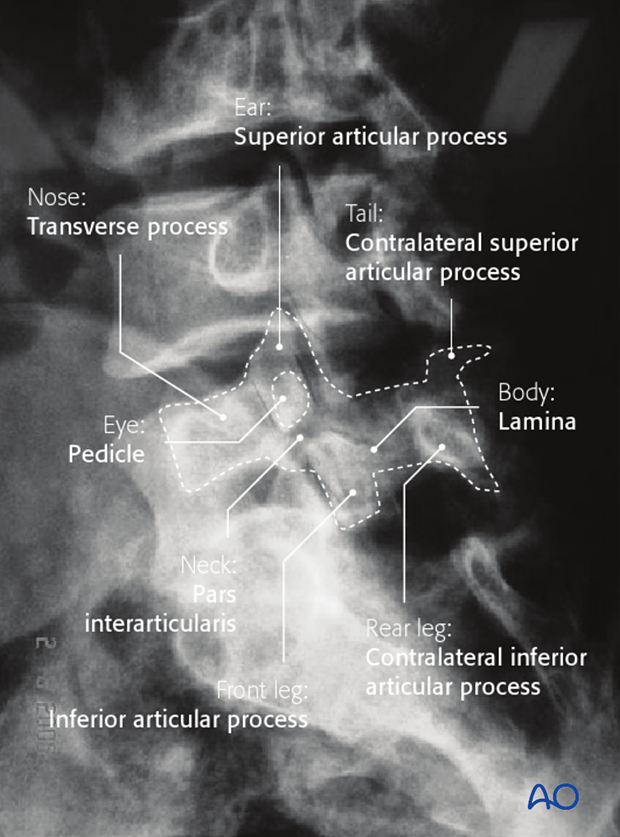

approach to lumbar xrays

ABCCP

Alignment

follow corners of vertebrae from one level to the next

Bones

Cortical outline, VB height, integrity of pedicles & transverse pro.

Cartilage

IVD grad

Increase in height from sup-inf. L5/S1 narrower

Coverage

ensure entire lumbar spine is visible in each scan

Posterior Elements

check elements (Pedicles, lamina and Pars inter

Articularis)

pars interarticularis fracture

pars interarticularis (pars) lies between the superior and inferior articular process at each zygapophyseal/facet joint

usually L5 level

bilateral: spondylolisthesis

unilateral: spondylolysis